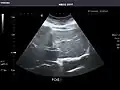

Right kidney -

Kidneys: Right and left kidneys measure 11.5 cm and 12 cm in length respectively. No hydronephrosis. Small left lower pole kidney cyst.